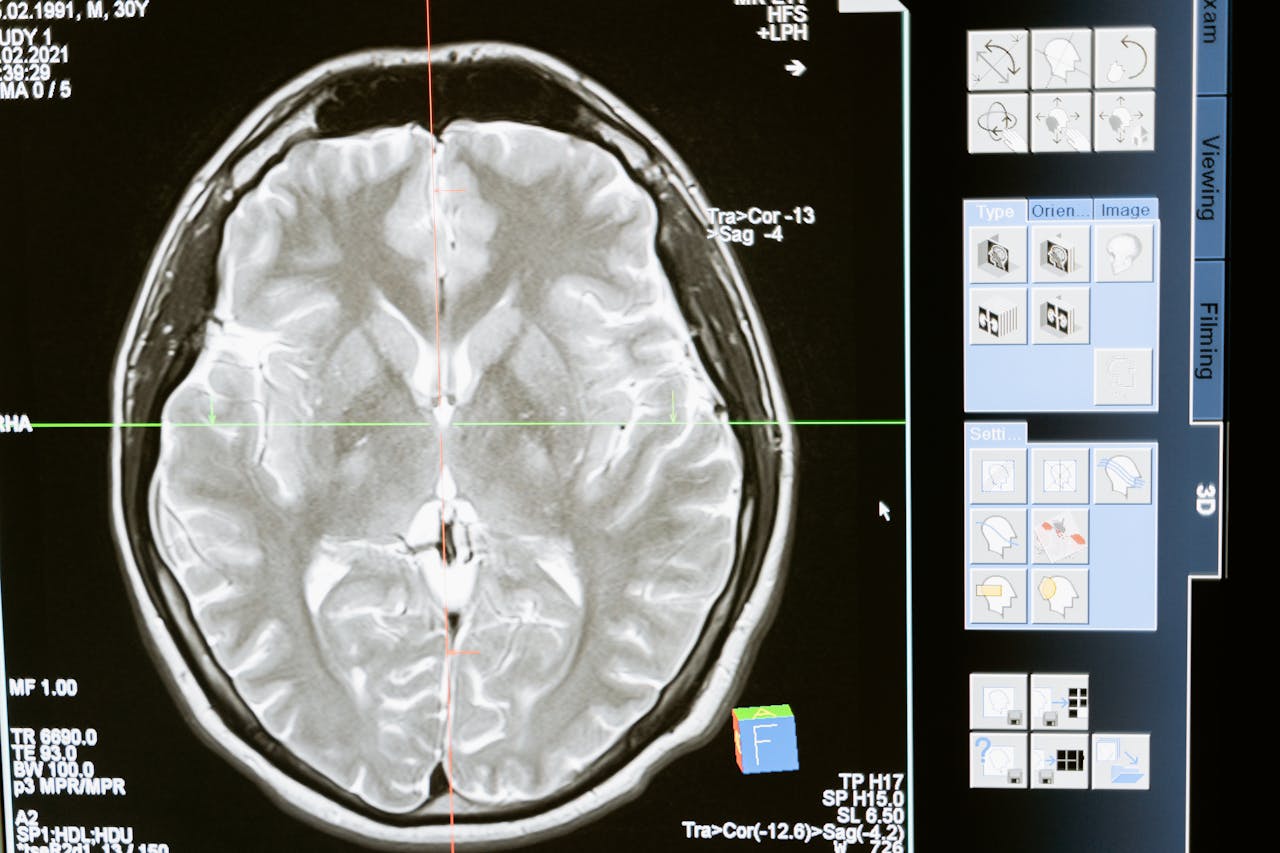

Zmysł węchu jest ewolucyjnie jednym z najstarszych i najbardziej pierwotnych. W przeciwieństwie do innych zmysłów, sygnały zapachowe omijają racjonalne filtry kory mózgowej i trafiają bezpośrednio do układu limbicznego – centrum odpowiedzialnego za emocje, pamięć i instynkty. To właśnie tam syntetyczne aromaty rozpoczynają swoją grę. Intensywne, proste kompozycje chemiczne potrafią w sposób niezwykle skuteczny stymulować mózgowy ośrodek nagrody, prowadząc do wyrzutu dopaminy.